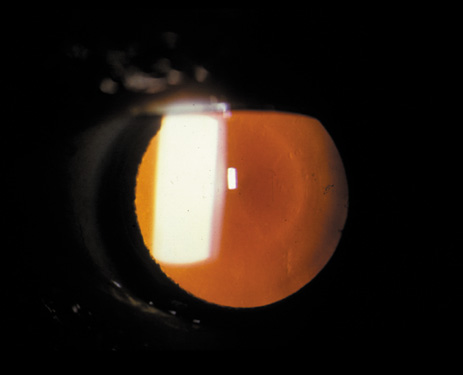

Nuclear cataracts tend to progress slowly. The refractive index of the lens changes as the nucleus progressively hardens, which usually results in increasing myopia.20,21 In some patients this is accompanied by optical distortion, especially of distant images, while near vision remains unaffected. A nuclear cataract is best seen with the narrow-beam direct illumination employed by the slit-lamp, which reveals the color and generalized haze or opalescence of the nucleus. In the early stages, the two halves (cotyledons) of the embryonic nucleus remain visible (Fig. 3). Later the entire nucleus appears as a homogeneous mass in contrast to the cortex (Fig. 4). Retroillumination may show the “oil droplet” effect (Fig. 5). Sometimes one may notice crystals in the lens nucleus (known as a Christmas tree cataract; Fig. 6A and B).

Fig. 3. Early nuclear cataract. Note the “cotyledons” in the nucleus.

Fig. 4. Advanced nuclear cataract. Note the homogeneous nuclear opacity.